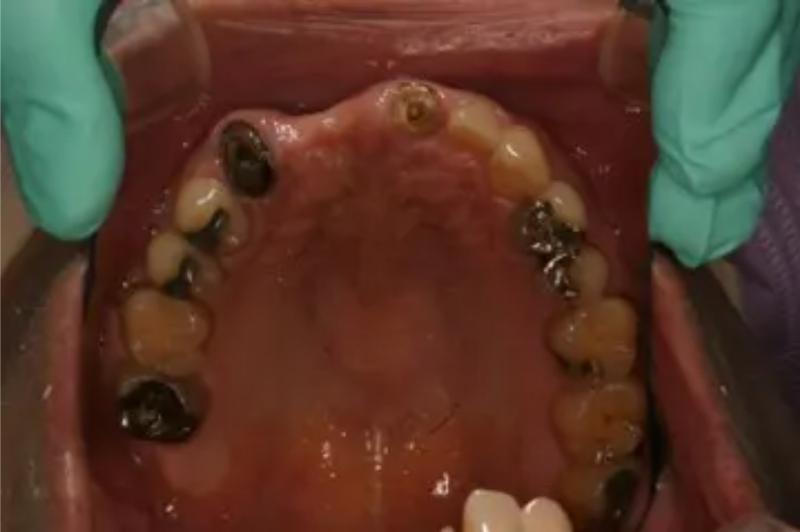

インプラント治療の症例紹介⑥

Before

After

主訴

咬めるようになりたい

治療内容

保存不可能な歯の抜歯、上下の咬み合わせを揃えて欠損部にインプラント治療

治療費

2,508,000円(税込)

治療期間

19ヶ月

通院回数

26回

想定されたリスク

※血糖値の高い方で、咬めるようになると高血糖となる可能性があるため食事制限が必要となる。インプラント周囲炎の恐れがありました。

歯の欠損による対合歯の挺出等を修正し咬合平面を揃えた症例